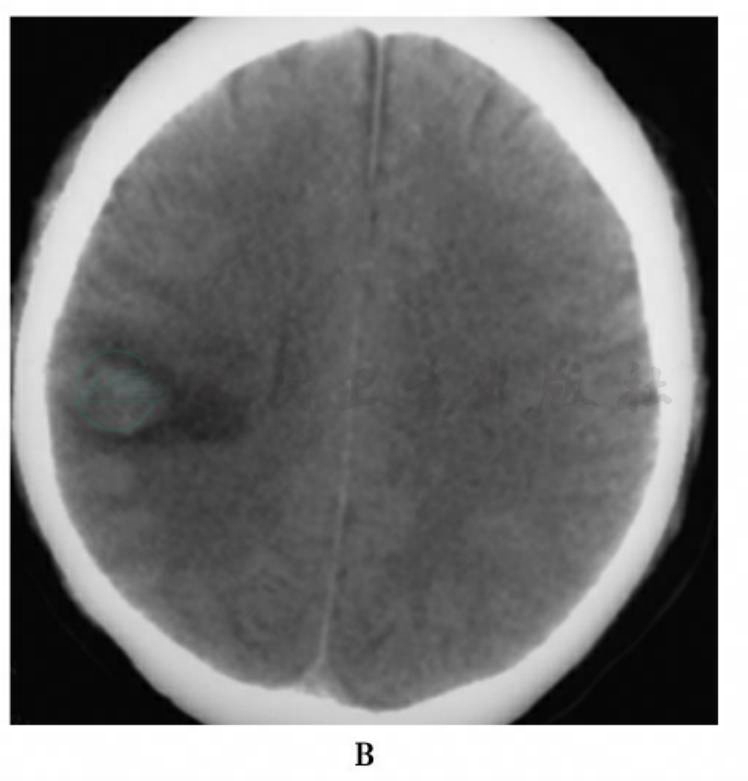

辅助检查:三大常规、生化、肝肾功能、DIC套餐未见明显异常。胸片正常。心电图:①窦性心律不齐+过缓;②交界性逸搏心律伴不完全性干扰性房室脱节;③T波异常,符合前侧壁心肌缺血;④左室电压增高。头颅CT:2009-1-14:左侧岛叶脑软化灶;2009-1-19:①右额叶脑梗死;②左侧基底节区脑软化灶;2009-2-7:①右侧颞顶叶占位,灶周明显水肿,考虑脑脓肿可能性大;②左侧岛叶囊样低密度灶。见图1。

图1 头颅CT

A.2009-1-14 CT平扫;B.2009-1-19 CT平扫;C.2009-2-07 CT平扫;D.2009-2-07 CT增强